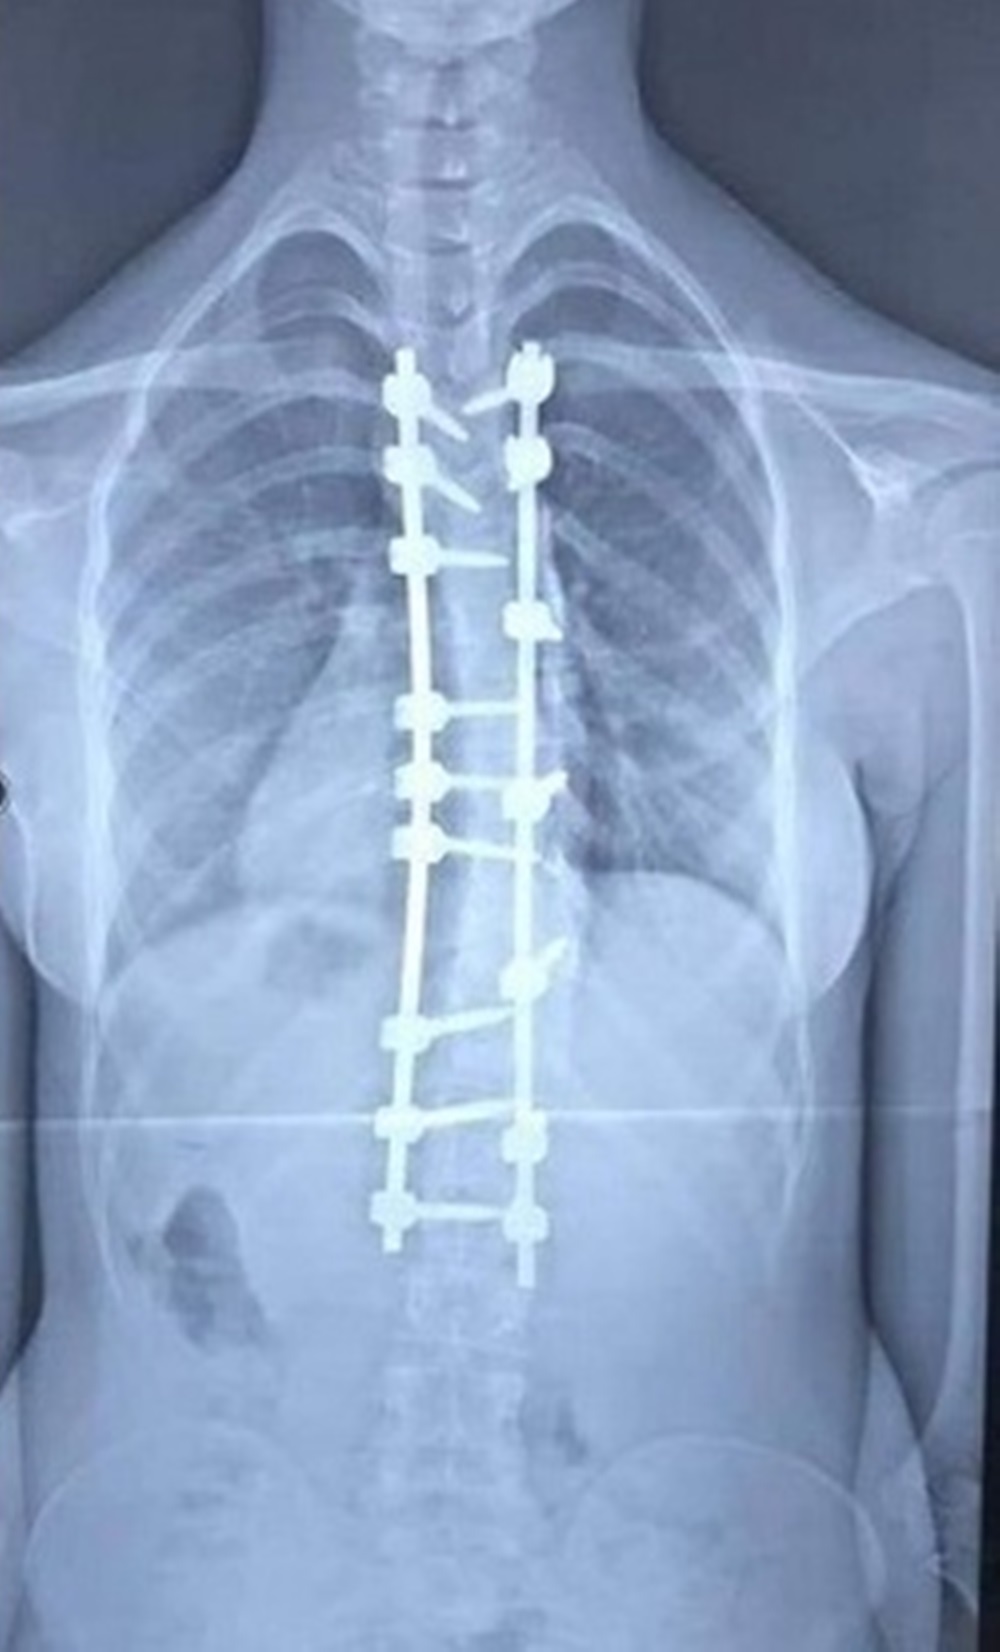

تعديل العمود الفقري لمريضة ستينية بعملية نوعية

أعلن فريق طبي في مستشفى الكفيل التخصصي بكربلاء، نجاحه بعملية تعديل جنف العمود الفقري لمريضة ستينية.

وقال إختصاصي جراحة العمود الفقري بالمستشفى الطبيب اللبناني، دكتور عامر السبعلي، في حديث صحافي، إن فريقنا الطبي نجح بعملية تعديل جنف العمود الفقري (إنحراف وتحدب العمود الفقري) لمريضة تبلغ من العمر (63) عاما، مبيناً إن الجنف بنسبة (35%)، وإن المريضة تعاني من تضييق في مجرى الدودة يرافقه آلام حادة جعلتها غير قادرة على ممارسة حياتها بشكل طبيعي.

وأشار السبعلي إلى، إن العملية إستغرقت خمس ساعات، بمساعدة فريق طبي متميز وأطباء تخدير ماهرين، فضلاً عن وجود التقنيات الحديثة التي شجعتنا على إجراء العملية، مؤكداً إن العملية كانت ناجحة والمريضة أستعادت إستقامة ظهره عقبها وهي الآن تتمتع بصحة جيدة.